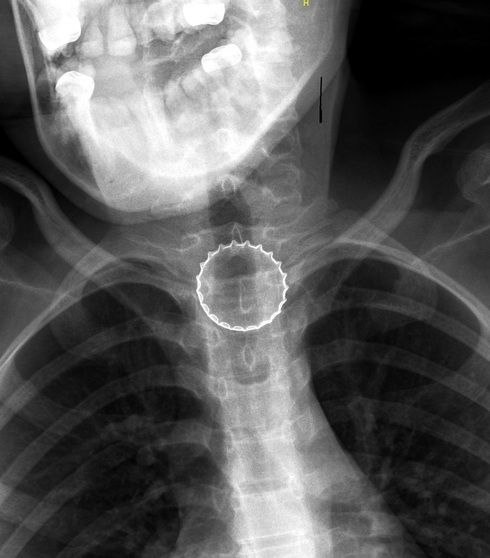

Челябинские врачи достали металическую крышку из пищевода подростка

В Челябинской областной детской клинической больнице провели операцию по извлечению металлической крышки, застрявшей в пищеводе 16-летнего подростка. Ситуация потребовала быстрой реакции врачей, так как возникла угроза повреждения внутренних тканей острыми краями крышки.

Подросток, играя, подбросил металлическую крышку от напитка и поймал её губами. В этот момент крышка случайно попала ему в горло и застряла в пищеводе, полностью перекрыв его. Сразу после инцидента подросток почувствовал дискомфорт и обратился за медицинской помощью в экстренное приёмное отделение ЧОДКБ.

Ситуация не позволяла откладывать вмешательство, поэтому мальчика направили на операционный стол. Операцию провела заведующая отделением эндоскопии Татьяна Лещёва. Вместе со своей командой Татьяна Юрьевна, используя видеоэндоскопическое оборудование, извлекла инородное тело из пищевода.

Острые зубчатые края крышки могли повредить слизистую оболочку и привести к кровотечению или разрыву пищевода. А толщина усложняла

Острые зубчатые края крышки могли повредить слизистую оболочку и привести к кровотечению или разрыву пищевода. А толщина усложняла захват инструментами, что требовало высокой точности манипуляций.